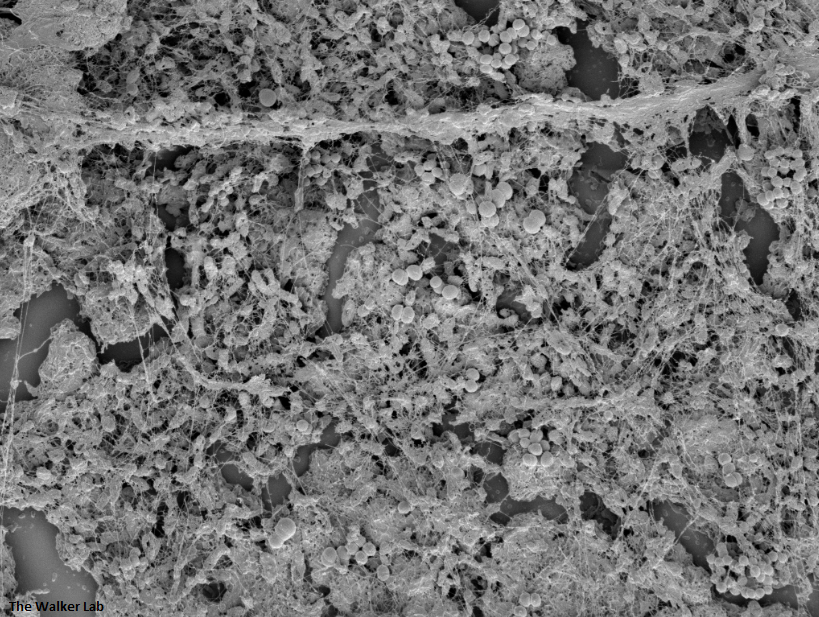

Host Immune Cells and Glycoproteins

The host inflammation response to the catheter recruits immune cells and wound healing proteins which are deposited on the catheter surface. Atypical pathogens can use these host factors to adhere to the catheter's large surface and create biofilm. Colonization of catheters occurs quicker than expected and develops even in the presence of prophylactic antibiotic therapy. MRSA is just one of the uropathogens that can attach to the altered urinary catheter surface. One host factor deposited on the catheter surface is fibrinogen. We recently discovered that MRSA binds fibrinogen to attach to the catheter surface and form biofilm, which increases antibiotic recalcitrance. Our future studies aim to develop new non-antibiotic strategies that interfere with those interactions to prevent or treat CAUTIs.